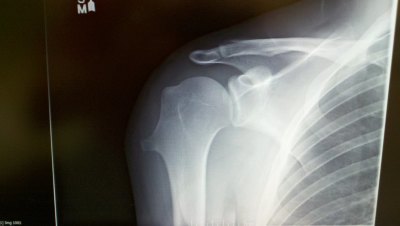

Its supposed to look like this...

Shoulder-Xray-752382.jpg